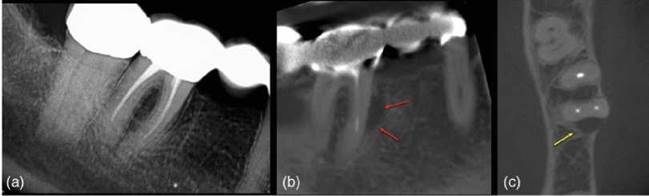

Early (incomplete) VRFs may not be read- ily detectable clinically or radiographically. However, as the VRF becomes more established and infected there will be widening of the periodontal ligament on one aspect of the root, in more advanced cases peri-radic- ular bone loss will be apparent [26]. A VRF will only be detected with conventional radiographs if the X ray beam is parallel to an incomplete fracture line (Figures 6.17 and 16.18). However, this is a rare occur- rence [18].

Figure 6.18 Vertical root fracture. (a) A periapical radiograph of the lower right molar teeth does not reveal anything untoward, however, the (b) sagittal (red arrows) and (c) axial (yellow arrow) CBCT slices reveal a clear radiolucency associated with the mesial root.

In cases where clinical and conventional radiographic examination are inconclusive CBCT may be useful in detecting subtle changes in peri-radicular bone adjacent to the site of a suspected VRF [91].